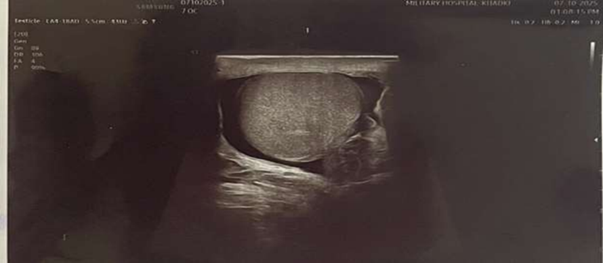

Follow-Up Scrotal Ultrasonography After Orchidopexy

Both testes showed normal shape, size, and echotexture with no focal lesions identified. The left epididymis appeared mildly enlarged, while the right epididymis was normal. Increased vascularity was noted in the left testis and epididymis. The pampiniform plexus was visualized normally, and no abnormal fluid collection was seen. Overall findings were suggestive of a viable left testis with preserved vascularity and postoperative changes, with no evidence of recurrent torsion or ischemia.

Figure 7: USG left testis post op.

Figure 8: USG Right testis post op.